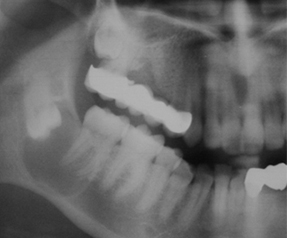

ÇENE CERRAHİSİ

KLİĞİMİZDE UYGULANAN ÇENE CERRAHİSİ TEDAVİLERİ